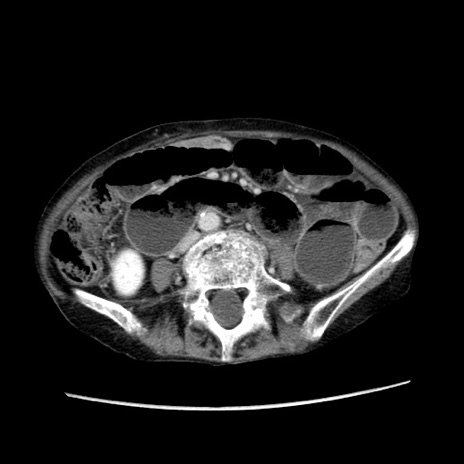

冠状断像

症例25(横断像)

【症例】80歳代女性

【主訴】胸のつかえ感

【現病歴】約9時間前に食後から胸のつかえた感じあり、嘔吐あり、来院。

【既往歴】胃癌(全摘)、胆摘、虫垂炎

【身体所見】心窩部に圧痛あり、反跳痛なし。

【データ】WBC 5700、CRP 0.05